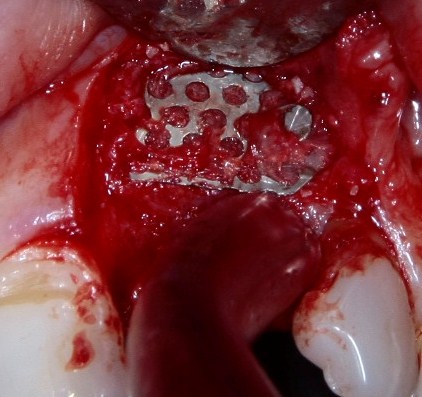

Что же касается нерезорбируемых мембран… Было дело, работал с Gore-Tex (дорого, очень дорого), титановыми сетками (заколебался потом доставать) и тефлоновыми Cytoplast:

результат:

или

с трудом выковыриваем сетку и ищем имплантат:

чтобы поставить формирователь:

Ну а, в целом же, не считая небходимости ОБЯЗАТЕЛЬНОЙ фиксации пинами или винтами, работа с нерезорбируемыми мембранами не отличается от работы с резорбируемыми коллагеновыми материалами. Поэтому особых преимуществ, способных повлиять на результаты лечения, у нерезорбируемых мембран нет.